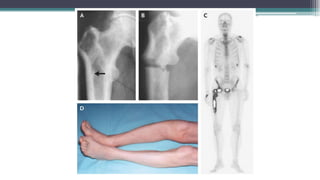

B- Imaging

1. X-ray

Bone rarefaction

Radiographic osteopenia

2. Bone scan: can show multiple hot spots in the ribs

and pelvis at the site of fractures and the appearance

may be mistaken for metastases